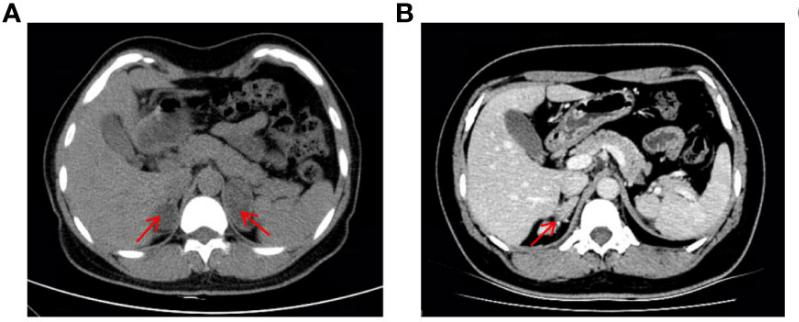

该患者是一名37岁的女性(核型为46 ,XX) ,童年时保存生长加速 ,且婚后一直未有身。2019年因疑诊双侧肾上腺肿瘤入院(图1A) ,前后举行了两次肾上腺切除术。2022年 ,患者由于月经不规则被收入内渗透科 ,CT显示右肾上腺皮质增生复发(图1B) ,体格检查显示该患者皮肤色素冷静 ,面部有痤疮和髯毛 ,泛起男性化体征 ,生化检查提醒低钾性高血压 ,高雄血症。均提醒11β-OHD诊断。

图1  患者腹部CT影像